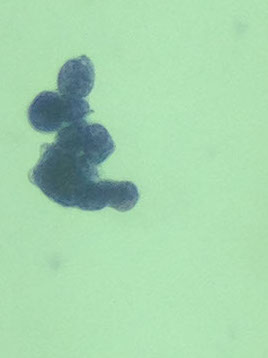

**in women is breast ca (CANON BALL!! [see image]), lung ca, lymphoma / leukemia

Papillary clusters (indicative of tumor implants), spherical clusters (sometimes called "morula" formations or proliferation spheres - a variant of the papillary cluster but highly suggestive of adeno, esp of the breast); dense nuclear branches (with scanty cytoplasm); enlarged nuclei (unusual inc in NC ratio); unusually large or elongated cells; Large red nucleoli; bizarre vacuolization (out of proportion to nuclear size); signet rings with molded nuclei; abnormal mitoses; sharp cellular borders; hyperchromasia

1) Large clusters with scalloped borders (“mulberry clusters”)

- “Windows” and “lacy skirts” like normal mesothelials

- Clusters of >20-40 cells are indicative of malignancy